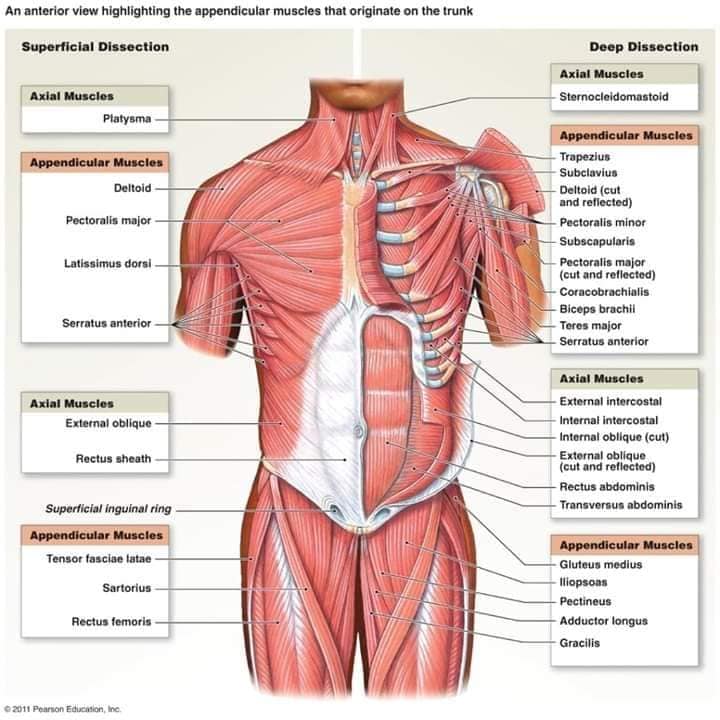

М'язова система людини є однією з основних систем організму, що відповідає за рухи, підтримання пози та стабільність. Вона складається з понад 600 м'язів, які можна класифікувати на скелетні, гладкі та серцеві м'язи. Скелетні м'язи, які є об'єктом нашого детального розгляду, дозволяють контролювати навколишній світ і виконувати різноманітні рухи. Особливу увагу в нашій статті буде приділено шейним і спинним м'язам, оскільки ці групи м'язів мають критичне значення для підтримання правильного постава та функціонування хребта.

Скелетні м'язи з'єднані з кістками за допомогою сухожиль і відповідають за більшість волевих рухів. Вони поділяються на:

- Швидкі м'язи - призначені для швидких і потужних рухів.

- Повільні м'язи - забезпечують стійкі і довготривалі рухи.

Скелетні м'язи мають поперечну смугасту структуру, що забезпечує їхню здатність до швидкого і ефективного скорочення.

Спинні м'язи виконують функції підтримки хребта, а також дозволяють здійснювати рухи тулуба.

Поверхневі спинні м'язи

М'язи, що піднімають лопатку: Трапецієподібний м'яз: великий м'яз, що покриває верхню частину спини. Його функція - підтримка і рух лопаток, а також забезпечення стабільності хребта.

М'язи, що ведуть лопатку до хребта: Широкий м'яз спини: великий м'яз, що розташований в нижній частині спини. Він відповідає за рухи плечей і лопаток, а також за розширення верхньої частини тулуба.